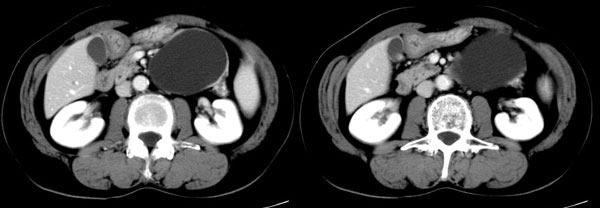

参照ct片,经皮穿刺,抽出透明液体60ml,随后置入引流管引流,囊液细胞学检查阴性,胰酶检查阴性。采用无水乙醇灌注治疗。4天后囊腔闭锁,无液体渗出,予以拔管。

置管后造影,显示囊腔直径约5cm,囊壁光整,正位、双斜位造影均未见造影剂外溢,与胰腺无交通